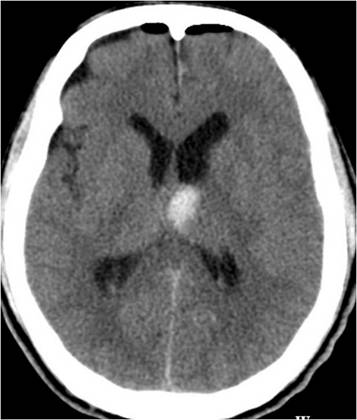

3个月前,某42岁患者无明显诱因出现头痛、头晕伴恶心呕吐,意识逐渐下降,在当地医院检查头部CT,提示:左侧脑室内出血,如图1;医生为其急诊实施“双侧脑室钻孔外引流术”。

图1,左侧脑室内出血(3个月前)